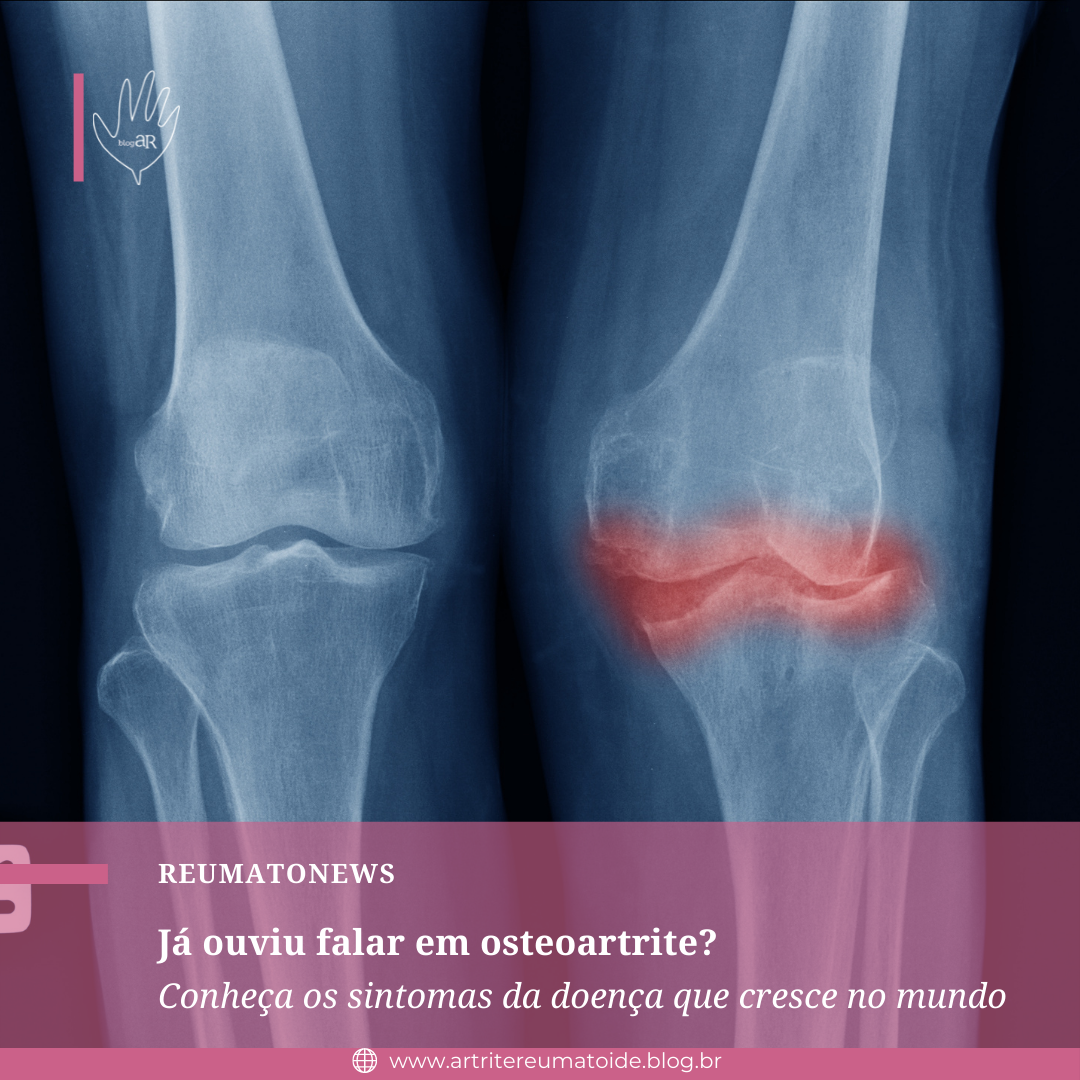

Você sabe o que é osteoartrite? Essa doença reumática é também conhecida popularmente como artrose ou osteoartrose. Muitas pessoas acreditam que se trata de um processo natural do envelhecimento. No entanto, a osteoartrite é uma doença causada pela insuficiência de cartilagem no corpo, acarretando em alterações nos membros acometidos.

No entanto, somente 30 a 50% dessas pessoas queixam-se de dor crônica. A osteoartrite se caracteriza pelo desgaste da cartilagem e por alterações ósseas. Entre essas alterações, estão os osteófitos, conhecidos popularmente por bicos de papagaio.

Ainda, as alterações na radiografia geralmente não correspondem aos sintomas apresentados pela pessoa. Ou seja, uma radiografia pode mostrar apenas uma pequena alteração em um indivíduo com sintomas graves, ou então pode apresentar inúmeras alterações em uma pessoa com poucos ou nenhum sintoma.